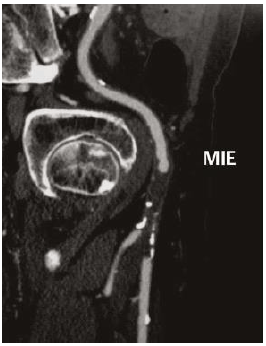

José Carlos, 64 anos, queixa-se de lesão dolorosa pós-traumática em extremidade do hálux esquerdo há 14 dias. Hipertenso, dislipidêmico e tabagista. Ao exame, ambos os membros inferiores apresentam pulso femoral 3/3+ e pulso poplíteo e distais ausentes. Hálux direito apresenta gangrena seca de sua extremidade. Comparece com o seguinte exame complementar solicitado pelo médico anterior:

Diante do exposto, assinale a alternativa que apresenta a conduta mais adequada para o caso.